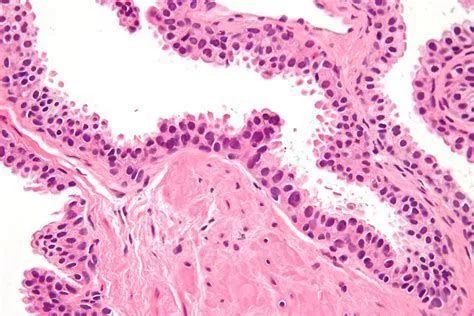

乳腺癌可以根据某些特殊的模式转移到其他器官,这是一项由瑞典卡罗林斯卡研究所、瑞典皇家理工学院(KTH)和芬兰赫尔辛基大学的研究人员发现的,他们通过研究癌细胞DNA对病人乳腺癌的转移途径进行了总结。相关研究成果于近日发表在《Journal of Clinical Investigation》上。

在这项新研究中,研究人员研究了20个病人的乳腺癌组织、腋窝淋巴结及其他器官的转移灶中癌组织的DNA。通过一种叫做下一代测序的新技术,研究人员绘制了乳腺中的癌细胞和其他器官的转移灶的关系。这使他们找到了癌症转移的途径。

这项研究表明癌细胞从乳腺癌组织中转移到腋窝淋巴结以及其他器官。下一步的转移灶通常从这些器官中转移。

“我们最重要的发现是腋窝淋巴结的转移灶似乎并不会进一步转移到其他器官,因此尽管这些转移灶可以展现出癌症的恶性程度,但是并不是它们引起了转移。” Johan Hartman说道。他是卡罗林斯卡研究所肿瘤病理系副教授,也是该研究的领导者之一。

他们还发现某些情况下乳腺癌中的癌细胞会同时在不同的器官形成转移灶。研究人员还揭示了乳腺癌的不同区域会引起身体特定的组织形成转移灶。